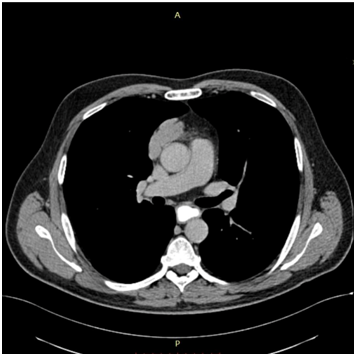

The 1st case we report is of a 22-year-old Caucasian male, who was admitted to our hospital with a 3-days history of progressive dyspnea on exertion, neck swelling, fatigue, persistent chest pain, pyrexia, and a cough that was occasionally productive of blood. The physical examination revealed a heart rate of 115 beats per minute (Sinus Rhythm), a respiratory rate of 25 breaths per minute and superficial vascular distention over the neck. Laboratory studies revealed elevated serum α-fetoprotein (AFP) (5380 IU/ml) and D-dimer (481ng/ml). A chest X-ray in the poster - anterior view, upon admission, depicted a suggestive right upper mediastinal mass (Bild 1). Radiography was followed by contrast-enhanced CT scan that revealed a large, homogeneous mediastinal mass crossing into the anterior mediastinum and compressing – encasing the superior vena cava. It also showed signs of thrombosis of the left brachiocephalic vein, and multiple filling defects at the left pulmonary artery indicating embolism. Subcarinal lymphadenopathy, as well as enlarged lymph nodes of the right hilum was present (Bild’s 2-5). On median sternotomy, a large non resectable tumor was observed involving the in nominate vein and the superior vena cava (Bild 6). Great care was taken to remove as much tumor mass as possible. To decompress the superior vena cava, we had to perform an extensive resection and reconstruction of the cephalad part of the superior vena cava using homolog pericardium.A histopathological examination of a section of the mass revealed a mixed NSGCT (embryonal yolk sac/endodermal sinus tumour), containing also elements of embryonal carcinoma (Figure 1-6).The patient was placed on cisplatin-based chemotherapy (BEP regimen: cisplatin 50mg/m2 on days 1-2, etoposide 165mg/m2 on days 1-3, bleomycin 30U on days 1, 8, and 15, every 3 weeks). Tumor markers were elevated for a-FP (214ng/mL) and normal for β-HCG. The patient completed 4 cycles of chemotherapy and the subsequent chest CT (Bild 7) revealed a partial remission of the mass (decrease>50% of the size). The a-FP was normal as well as the β-HCG. The remaining mass was inoperable so the patient was started on salvage chemotherapy with the TIP (paclitaxel, ifosfamide, ciplatin) regimen for 4 cycles. The post-chemo chest CT showed stable disease and the patient was referred to radiation oncologists for radiotherapy of the remaining tumor. Three months later af P was found elevated and the CTs revealed multiple brain metastases. Whole brain radiation was performed and the patient was placed on gemcitabine (d1 and d8 every 21 days). Two months later the neurologic status deteriorated with new brain metastases and the patient passed away (19 months after the diagnosis).

Bild 4 CT – axial plan demonstrating a 10cm Yolk sac tumor invading the truncus pulmonalis and the vena cava superior.

The 2nd case we report is of a 42-year-old Caucasian male who sought the gastroenterology outpatient clinic complaining of dysphagia for about 4 months. Laboratory findings were normal. X-ray with a contrast material (barium X-ray) and upper GI endoscopy were performed and the patient was treated for gastro-oesophageal reflux disease via lifestyle changes and oral medication with proton-pump inhibitors. Two months later the symptom had precipitated and after oesophageal pH monitoring was performed, surgical treatment was decided. Before the surgery, an MRI scan of the chest showed a large mass of the anterior and middle mediastinum (Bild’s 8-9). PET showed marked uptake only in the mediastinal mass. Fine needle aspirates and core biopsies yielded a poorly differentiated neoplasm. Blood tests for germ cell tumor markers showed a normal a-fetoprotein level and an elevated β-HCG level (31mIU/ml). Thoracoscopy was performed to obtain sufficient tissue and histopathological examination of a section of the neoplasia revealed a seminoma (Figure 7-12). Testicular sonography was performed to look for an occult primary tumor. The testicles were normally positioned and symmetric in size and echogenicity. No mass was present. Thoracotomy revealed a dark, solid mass adherent to the pericardium, which was removed. Patient was placed on cisplatin-based chemotherapy (BEP regimen: cisplatin 50mg/m2 on days 1-2, etoposide 165mg/m2 on days 1-3, bleomycin 30U on days 1, 8, and 15, every 3 weeks). Patient completed 4 cycles of chemotherapy without major hematologic toxicity. A subsequent chest CT revealed a decrease in the size of the middle mediastinum remaining mass (from 5,5x2,5 to 2,3x1,5cm). The fluorine-18, deoxy-2-fluoro-d-glucose positron emission tomography (PET)–computerized tomography (CT) (PET–CT) was negative for viable disease. The remaining mass was inoperable so the patient was offered follow up with 3monthly chest CT and tumour markers (b-HCG, aFP, LDH) for the first year, 4monthly for the second year and twice a year for years 4,5 and 6. Today, 76 months after the diagnosis the patient is in perfect health without any signs of relapse.